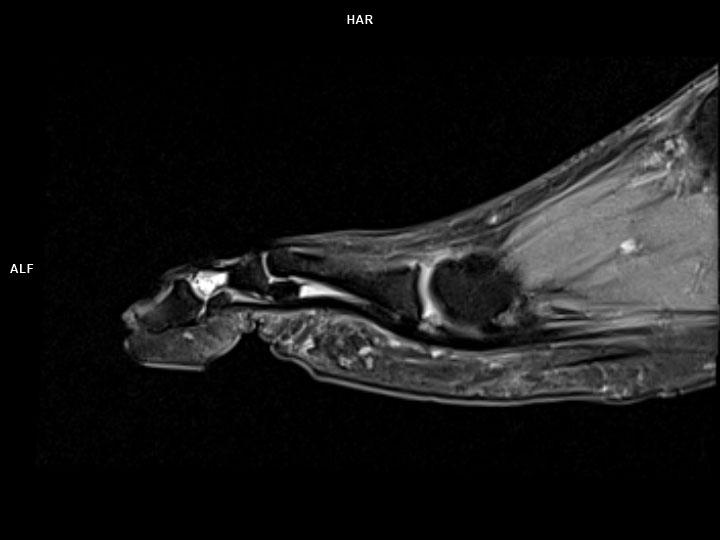

Sagittal PD FS-MAGNETOM Lumina

Sagittal PD FS-MAGNETOM Lumina/Coil-Foot Ankle 16/Resolution-352/Scan Time-3:22